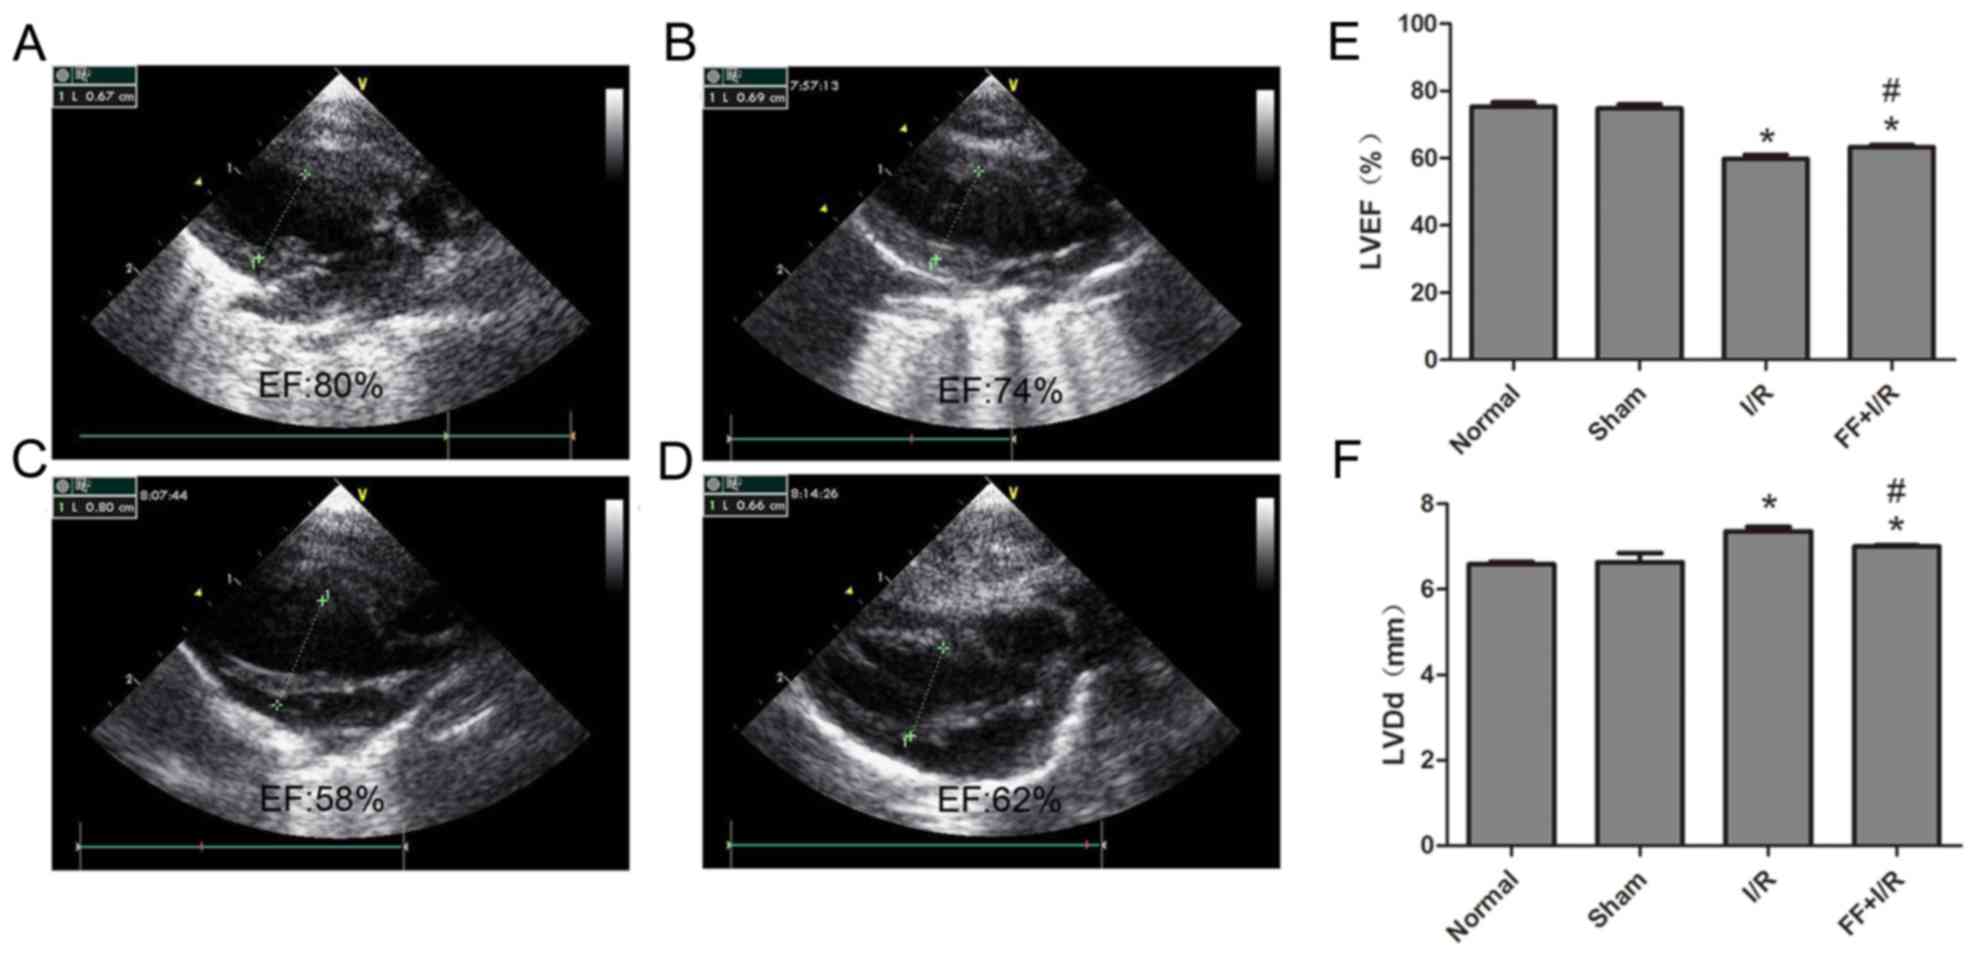

Heart functional examination

Standard echocardiography was performed at room temperature for all groups of rats following 45 min acute myocardial ischemia and 120 min reperfusion. The left ventricular ejection fraction (LVEF) and left ventricular end-diastolic diameter (LVDd) were measured from the parasternal long-axis view at the mid-papillary muscle level with an ultrasound imaging system (Vevo770; FUJIFILM Visual Sonics, Inc., Toronto, ON, Canada).

Cardiac function of each group

The cardiac function of each rat (n=8) was examined by echocardiography. Compared with the normal group, the values of LVEF and LVDd had no significant differences in the sham group (normal, 75.25±3.81 vs. sham, 74.75±3.61, P>0.05; normal, 6.59±0.16 vs. sham, 6.64±0.60, P>0.05). Compared with the sham group, the values of LVEF in the I/R group and FF+I/R group were lower, while the LVDd values were higher (all P<0.05). Furthermore, compared with the I/R group, the values of LVEF in the FF+I/R group were higher (I/R, 59.75±3.62 vs. FF+I/R, 63.25±2.05, P<0.05), and the LVDd values were lower (I/R, 7.33±0.16 vs. FF+I/R, 7.00±0.19, P<0.05) (Fig. 2).

Figure 2.

Effect of FF on cardiac function in rats with acute I/R. Echocardiograms of rats in the (A) normal group, (B) Sham group, (C) I/R group and (D) FF+I/R group. (E) The LVEF of rats in each group. (F) The LVDd of rats in each group. Data are presented as the mean ± standard error (n=8). *P<0.05 vs. sham group; #P<0.05 vs. I/R group. I/R, ischemia/reperfusion; FF, pretreatment with fenofibrate; EF, ejection fraction; LVDd, left ventricular end-diastolic diameter; LVEF, left ventricular ejection fraction.